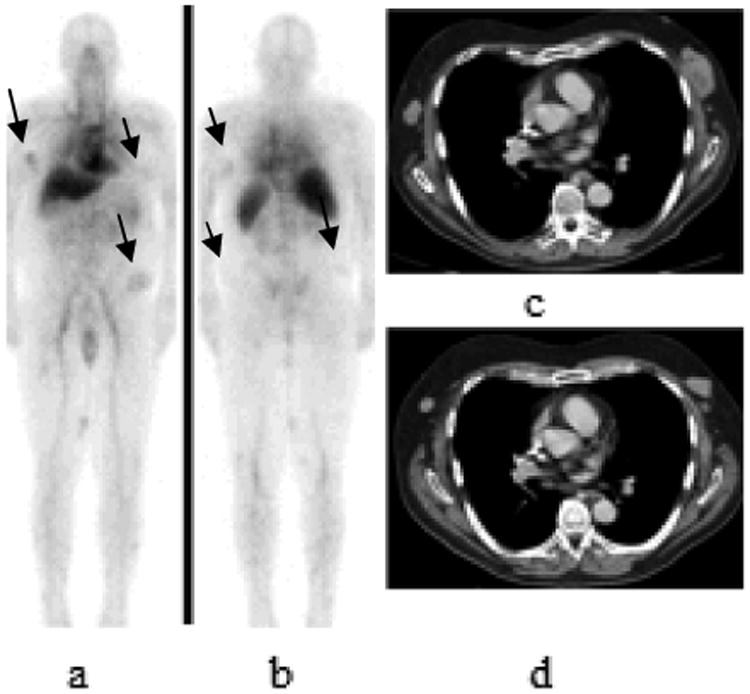

Figure 6.

68 year old patient with history of CLL with Richter transformation from B lineage chronic lymphocytic leukemia to diffuse large B-cell lymphoma with 111In- ibritumomab tiuxetan uptake seen on lymphoma lesions. 111In- ibritumomab tiuxetan whole body planar 48 hours images anterior and posterior views (arrows in a and b) show uptake in subcutaneous nodules consistent with lymphoma involvement. Axial contrast- enhanced CT images show multiple subcutaneous masses. This patient presented with progression of the disease at 3 months posttreatment with increase in size of subcutaneous lesions on follow-up CT scan (image c) compared to pretreatement CT scan (image d).